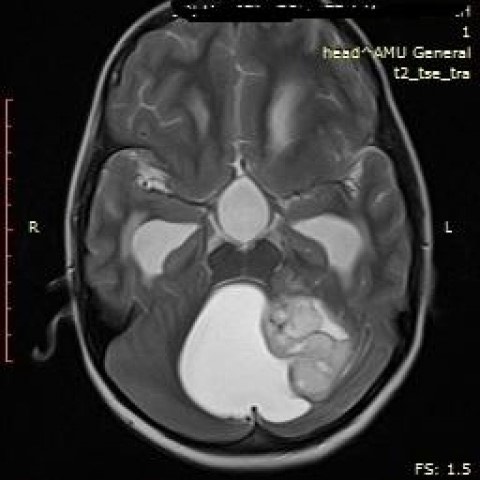

3811. Мальчику 14 лет с головной болью, дисметрией и адиадохокинезом выполнена магнитно-резонансная томография, заболеванием, которое может соответствовать клинико-рентгенологической картине, считают